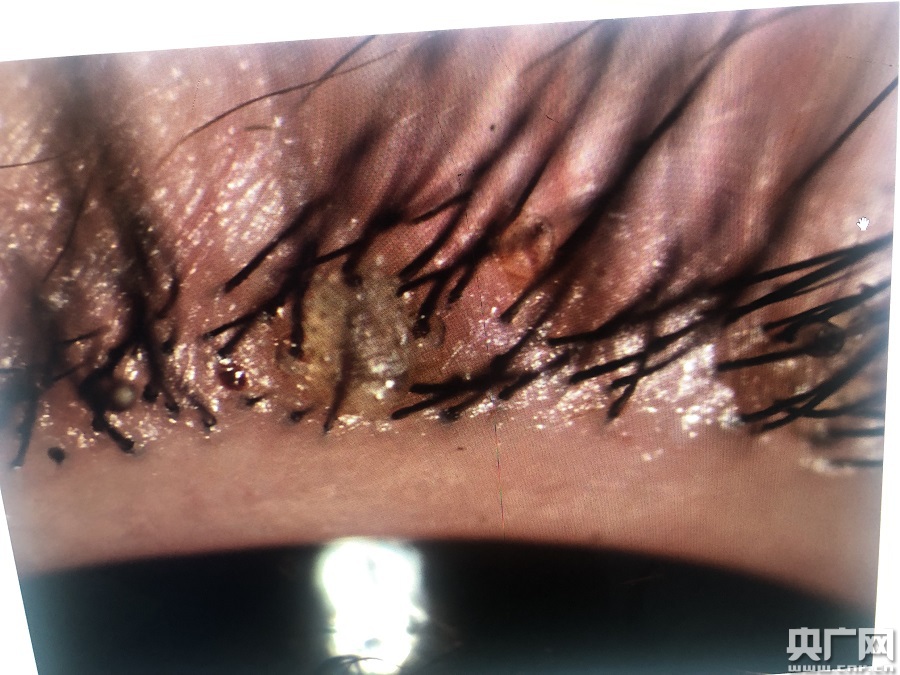

小女孩眼睫毛上長(zhǎng)滿陰虱(央廣網(wǎng)發(fā) 通訊員供圖)

該院眼表及角膜病?聘敝魅吾t(yī)師商旭敏接診后,在裂隙燈下仔細(xì)查看,發(fā)現(xiàn)甜甜的雙眼局部紅腫明顯,睫毛根部竟然掛著幾十粒黑色未孵化的蟲卵及白色孵化后的卵殼。仔細(xì)觀察之下,還有白色的蟲子在蠕動(dòng)。

該院門診副護(hù)士長(zhǎng)王亞靈先在裂隙燈下夾起吸附在瞼緣上的陰虱、蟲卵,剪去睫毛,反復(fù)確認(rèn)陰虱和蟲卵全部除盡后,再進(jìn)行局部清洗、上藥!敖(jīng)查實(shí),這些小蟲子是陰虱,有20多只。取出的睫毛、成蟲還有蟲卵都進(jìn)行統(tǒng)一焚燒。我從醫(yī)幾十年,有見過(guò)眼內(nèi)長(zhǎng)陰虱的,不過(guò)長(zhǎng)20多只,這還是第一次碰到!蓖鮼嗢`說(shuō)。